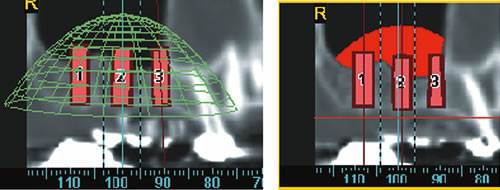

Abb. 5.7: Implantations- simulation am PC.

Abb. 5.8: Implantatplanung.

Dabei werden das Implantat, die richtige Länge und der geeignete Durchmesser ausgewählt. Entscheidend ist auch die Richtung, in der implantiert werden muss. Auch dies lässt sich bereits am Computer auf den Schnittbildern simulieren. Eine dreidimensionale Darstellung des Knochens und die Möglichkeit das äußere Profil zu zeigen, verdeutlichen den späteren Sitz der Implantate und die Beziehung zum Gegenkiefer, zur Kauebene, zu Wangen und Lippen lassen die spätere Versorgung kosmetisch vorhersehen (Abb. 5.9, 5.10). Eine Dichtemessung um die Implantate schließt die Planung ab.

Abb. 5.9: Dreidimensionale Darstellung der geplanten Implantate im knöchernen Anteil.

Abb. 5.10: Dreidimensionale Implantatplanung und Lagebeziehung zu Wangen und Lippen.